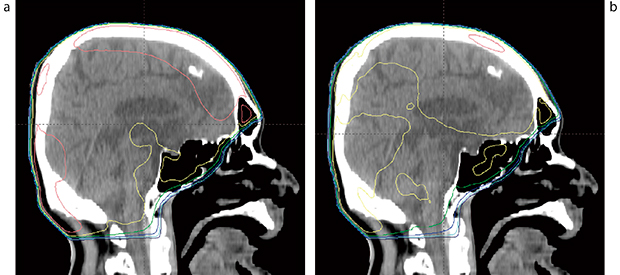

3.Flattening Filter Free(FFF)ビームによる平坦度の改善

TrueBeamの導入により,照射野中心に比べ周辺の線量が高すぎる場合,適当な重みでFFFビームを加えて平坦度を改善できるようになった。特に全脳照射で有用であり(図4),進行食道がんの放射線治療でもFFFビームで頸部や腹部の過線量を軽減できる場合がある(図5)。

図4 FFFによる全脳照射の平坦度改善

a:10MVX線左右対向2門照射では,ピーク線量は照射野中心の110%に達する。

b:10MVFFFX線を12%混合することで,ピーク線量は106.1%に低下した。